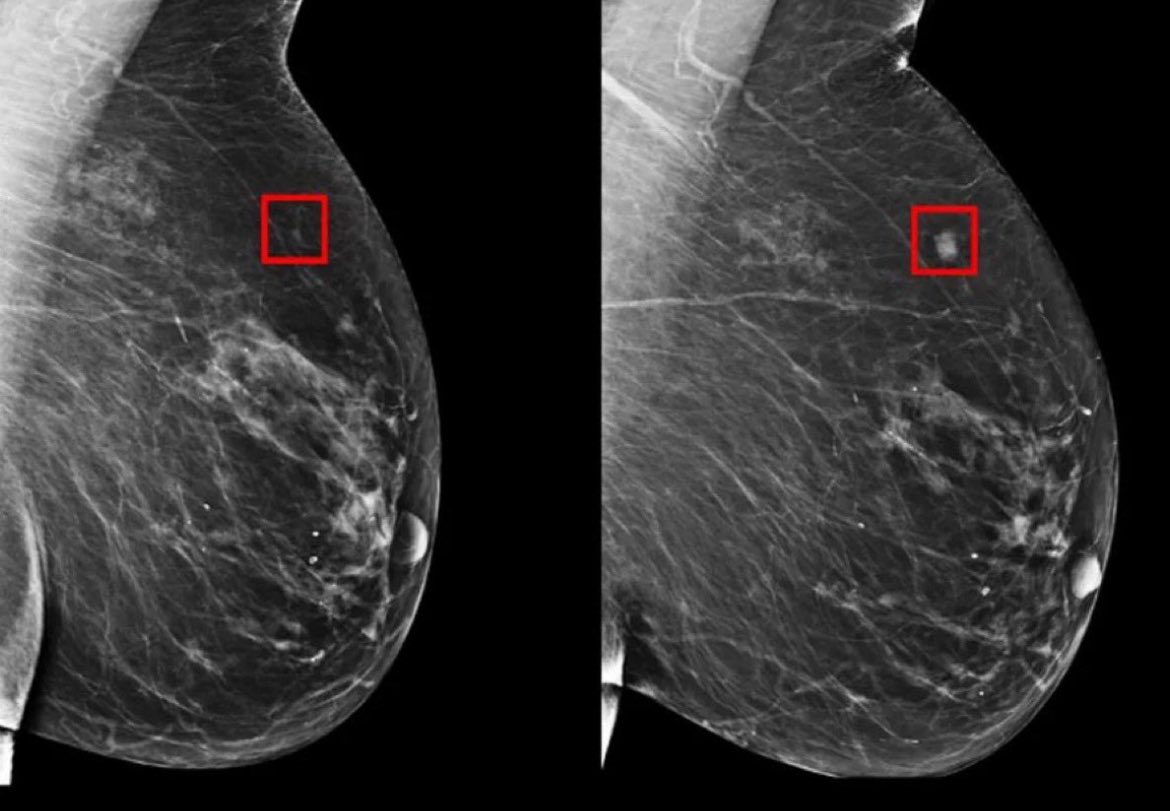

Mirai, le modèle d’IA qui sauve des vies

<strong>Détecter le cancer du sein bien avant qu’il ne se développe, c’est désormais possible grâce à un nouveau modèle d’intelligence artificielle. Développé par des experts en technologie médicale et validé à l’échelle internationale, ce système, baptisé Mirai, pourrait bien révolutionner le dépistage précoce du cancer et améliorer significativement les chances de survie de milliers de femmes.</strong>